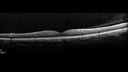

Perifoveal Microaneurysm - Not Diabetic (also reticular pseudodrusen)358 views87 year old female with fluctuating macular edema in the right eye from a perifoveal MA. (no treatment). VA 20/40 OUApr 02, 2020